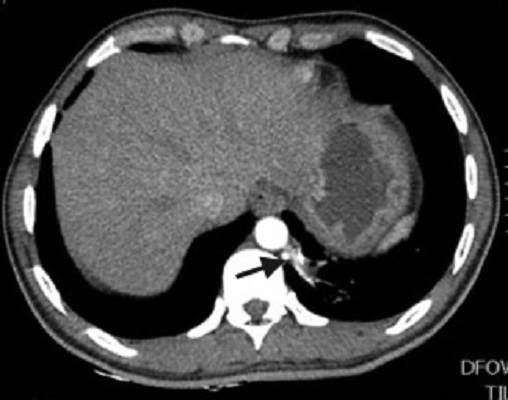

Paciente de 39 años con antecedente de Síndrome de Tolosa Hunt, quien ingresa al servicio de urgencias por disminución de la agudeza visual y cefalea. Dado el antecedente se considera realizar estudios complementarios para descartar enfermedad granulomatosa, como causa del síndrome, encontrando hallazgos incidentales en las imágenes del tórax. El secuestro pulmonar es una anomalía congénita caracterizada por tejido pulmonar displasico, sin conexión normal con la vía aérea, irrigado por la circulación arterial sistémica. Hay dos tipos de secuestros, el intralobar y el extralobar. El intralobar (75%), puede ser congénito o adquirido como secuela de infecciones recurrentes localizadas, está cubierto por pleura del pulmón normal adyacente y generalmente su drenaje venoso es a través del sistema venoso pulmonar ipsilateral. El secuestro extralobar (25%), es considerado una anomalía congénita, está revestido por su propia pleura y su drenaje venoso es sistémico. Tanto el secuestro intralobar como extralobar reciben suplencia arterial sistémica. En los estudios de imágenes, el secuestro se puede presentar como consolidación focal, nódulo o masa, de localización paravertebral, contiguo al hemidiafragma, en los lóbulos inferiores (segmento posterior), con mayor frecuencia en el lado izquierdo (98%) y con una suplencia arterial anómala dada por una o múltiples ramas (15%) generalmente de la aorta torácica y su drenaje puede ser al sistema venoso pulmonar y con menor frecuencia a la circulación sistémica.